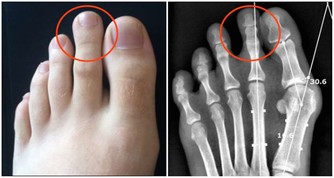

容易產生輕度疾病

具有調節體溫機能的腦下視丘,同時也是控制自律神經及激素的中樞。因此,低體溫會影響自律神經功能以及激素平衡,進而引起肩膀僵硬、頭痛、暈眩、手腳冰冷等症狀。另外,體溫偏低與月經不調、經前症候群等婦科病也有關聯。